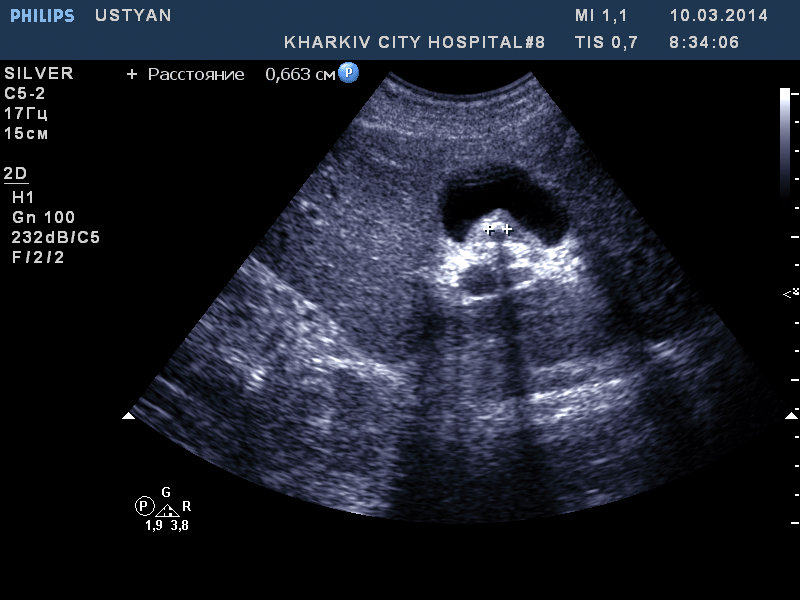

в общем не совсем понятно содержимое желчного. Полип есть. Вопрос вот в чем- как трактовать: загустевшая желчь и в ней конкремент или это не сладж, а образование? конкремент тогда каким образомтам ? как то смущает картинка.

я повторно смотрю пациента. В первый раз у него была загустевшая желчь хлопьями и я данную структуру расценил как сладж и конкремент внутри. Теперь хлопьев нет и как-то теперь не сильно на сладж похоже.

у пациента гепатит С.

Такой сладж бывает, и, действительно, иногда напоминает полипы. Цветовой и Э доплер обычно не помогают. Действительно, полезен повторный осмотр через сутки-двое.